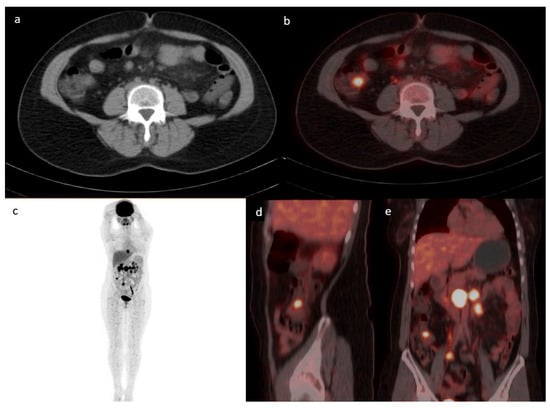

3.2. Location of Uptake

The most common location for incidental GIT uptake was in the upper GIT (n = 212; 48%) followed by the lower GIT (n = 147; 33%), with the rest showing an intestinal or mixed pattern of uptake. One example of lower GIT uptake is presented in Figure 2. The location of upper GIT uptake was in the following order: stomach (174/340; 51%), esophagus (97/340; 29%), and small intestine (69/340; 20%), with 38% (128/340) of the uptake showing multiple localizations in the upper GIT. The location of lower GIT uptake was in the following frequencies: sigmoid colon (77/194; 40%), ascending colon (49/194; 25%), transverse colon (36/194; 18%), descending colon (33/194; 17%), and rectum (1/194), with 25% (47/194) of the uptake showing multiple localizations in the lower GIT.

Figure 2. Case of a 43-year-old female with a history of follicular lymphoma. Axial CT (a) fused with PET (b) showing a focus of increased uptake at the level of the ileocecal valve with an SUVmax of 7.1 corresponding to a 1.7 cm soft tissue density. MIP (c) showing multiple active supra and infra diaphragmatic lymph nodes. The infra diaphragmatic lymph nodes are seen again in the fused sagittal (d) and coronal (e)-fused PET/CT images. The patient underwent a colonoscopy where ileal biopsy showed non-necrotizing granulomas, with no evidence of lymphoma or microorganisms.